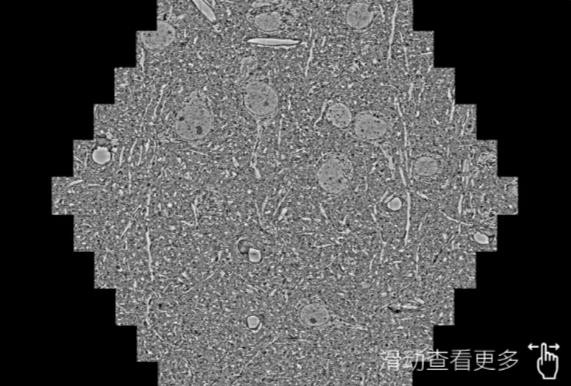

鼠脑切片。左图使用汉中蔡司汉中扫描电镜MultiSEM706对165μmx143pm面积区域成像,耗时仅需1.5秒。右图为鼠脑切片中30μm区域放大效果。样品由芝加哥大学B.Kasthuri提供。

使用蔡司高速汉中扫描电镜MultiSEM对1mm²人脑皮层组织进行高分辨成像,并对其中的各种细胞结构进行三维重构分析。左图展示了2x3mm²组织平面中锥体神经元的三维重构效果。右图显示了局部体积神经元三维重构。图像由哈佛大学chtman实验室提供,渲染图由D. Berger 制作。